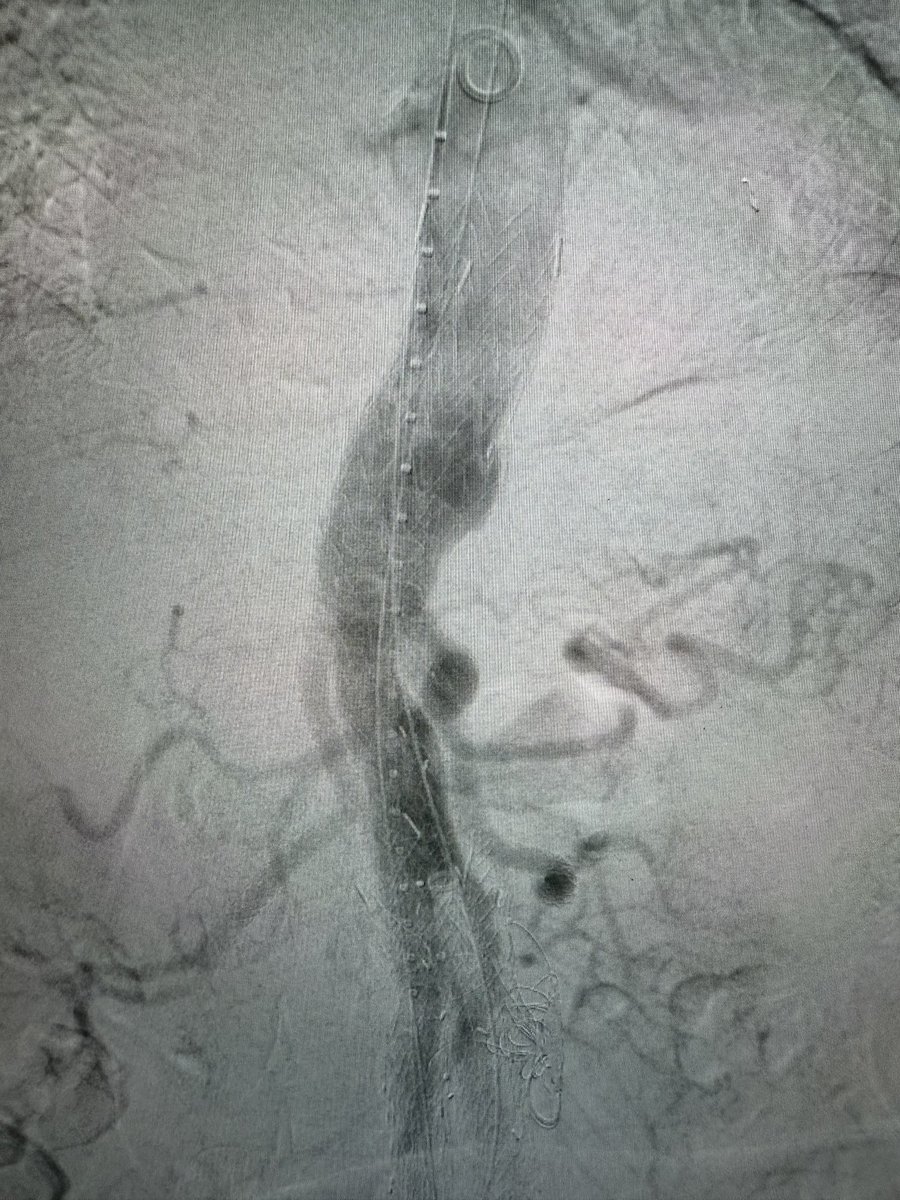

Dr Michael Wilderman

Chief of Endovascular Surgery and Co-Director of Aortic Center at Hackensack University Medical Center